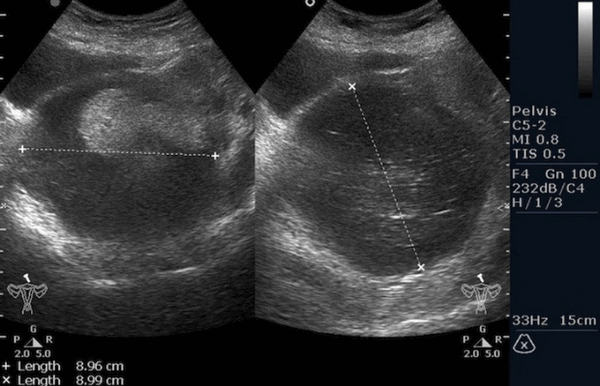

Рисунок 3. - тератома яичника а -УЗИ, б — МРТ.

- УЗИ. «Ультразвук» нужен для того, чтобы выявить первичный очаг как гонадной (в половых органах), так и внегонадной герминогенной опухоли. Его также проводят в ходе терапии, чтобы оценить ее эффективность.

- КТ (расшифровка: компьютерная томография), МРТ (расшифровка: магнитно-резонансная томография), ПЭТ-КТ (расшифровка: позитронно-эмиссионная томография, совмещенная с КТ). Эти обследования необходимы, чтобы рассмотреть структуры организма послойно и визуализировать опухоль. Они показывают, как сильно распространен патологический опухолевый процесс на находящиеся рядом ткани и органы, есть ли поражение костей. КТ - это самый чувствительный метод для обнаружения метастазов в легких. Проведение МРТ и КТ головного мозга необходимо, чтобы обнаружить и визуализировать герминогенные новообразования эпифиза.